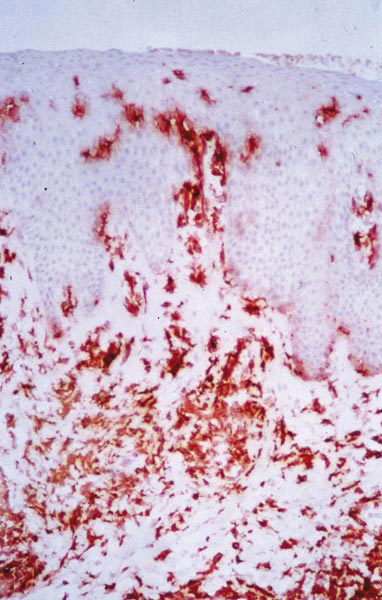

Les cellules rouges dans le derme superficiel et dans l’épiderme sont des lymphocytes T (immunomarquage par anticorps monoclonal anti-CD3). Les lymphocytes T jouent un rôle capital dans le déclenchement et le maintien de l’inflammation au cours du psoriasis. 3 Dans le derme, on retrouve une infiltration de lymphocytes T, principalement CD4+, de type mémoire, CD45 RO+, et de cellules mononucléées, associés plus tardivement à des polynucléaires neutrophiles.